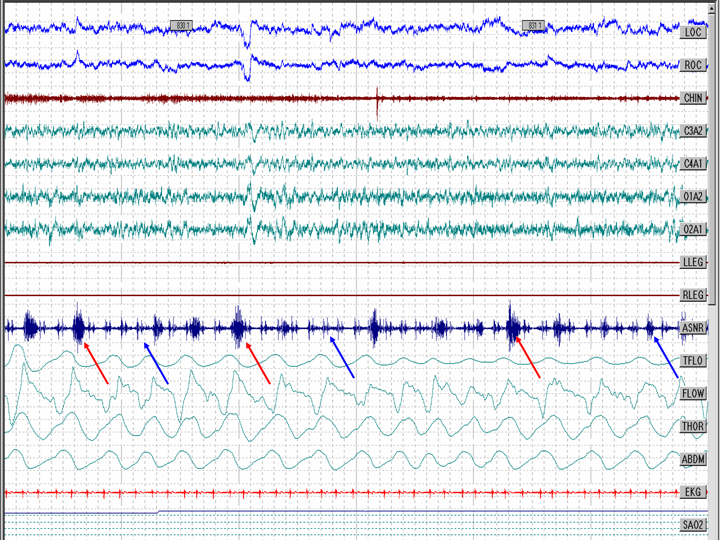

The figure shows a 30 second epoch from a sleep study. The red arrows represent snoring; the reader can recognize these events as snoring events because the events line up with the flow channel. The blue arrows represent pulse artifact in the snoring channel; the reader can recognize these events as pulse artifact because the events line up with the ECG channel. The snoring channel used in this recording is attached to the chin; if placed near the carotid artery, pulse artifact can be evident. To distinguish between true snoring and pulse artifact, the reader can correlate the events with one of the respiratory channels (snoring event) or the ECG channel (pulse artifact).

Abbreviations: LOC: left oculogram; ROC: right oculogram; CHIN: chin EMG; C3A2, C4A1: central EEG leads; O1A2, O2A1: occipital EEG leads; LLEG: left leg EMG; RLEG: right leg EMG; ASNR: snoring channel; TFLO: thermistor flow channel; FLOW: nasal pressure flow channel; THOR: thorax effort channel; ABDM: abdominal effort channel; EKG: electrocardiogram; SAO2: oxygen saturation channel.